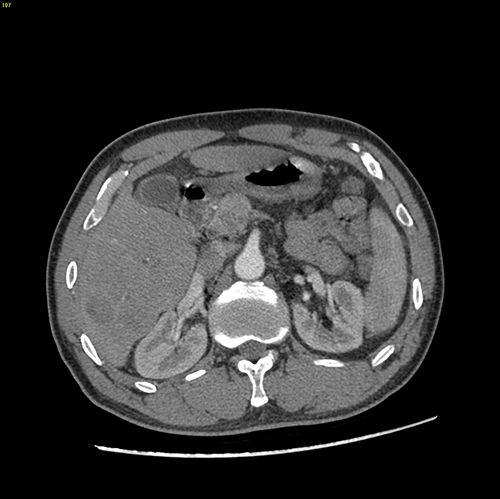

右肝癌、门静脉癌栓----右半肝切除,门静脉癌栓取出术

手术规划--右半肝切除,门静脉取癌栓